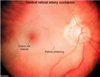

Lateral Geniculate Nucleus of the Thalamus

- From which tracts does it recive input?

- What sensations is it responsible for?

1.

Optic nerve (CNII), Optic chiasm, Optic Tract

2.

Vision

“Lateral see the Light“